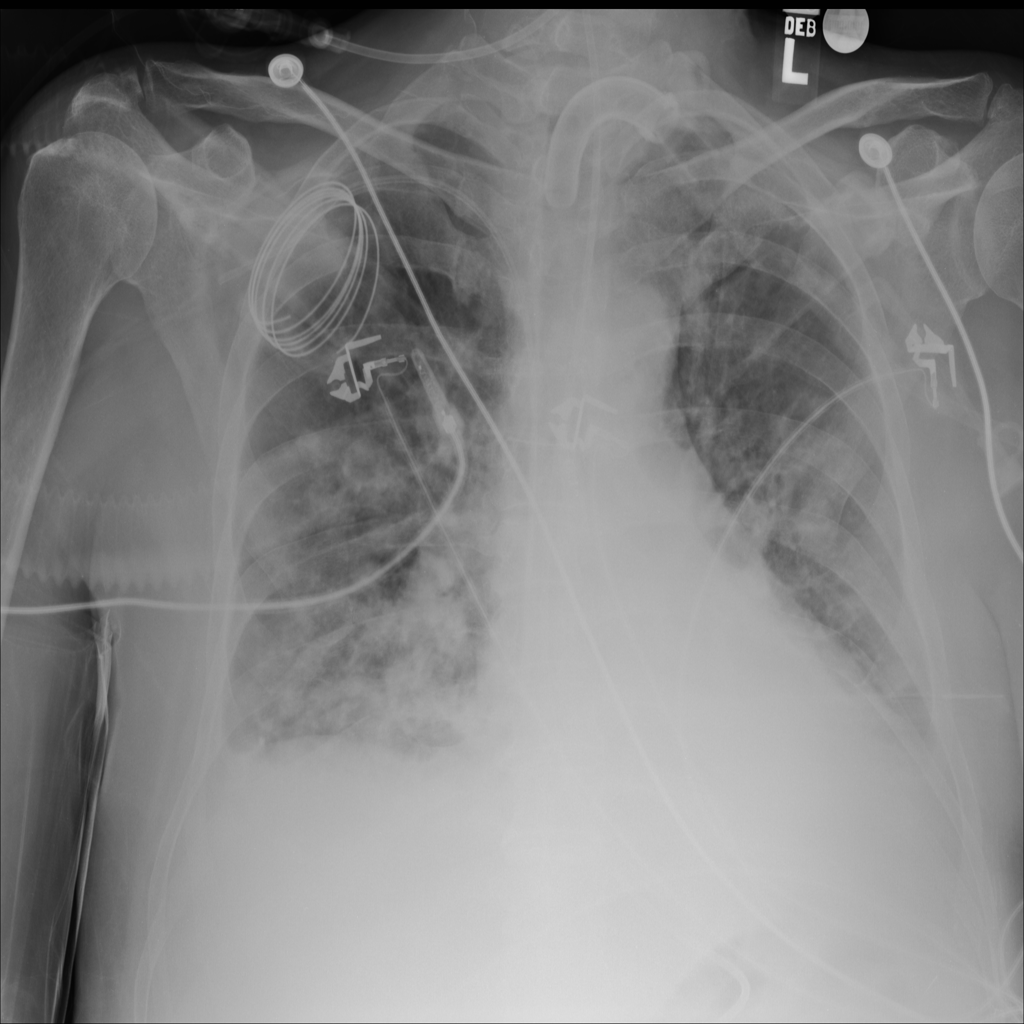

PAT-C1A7 · IMG-055Consolidation

PAT-C1A7 · IMG-055

AP